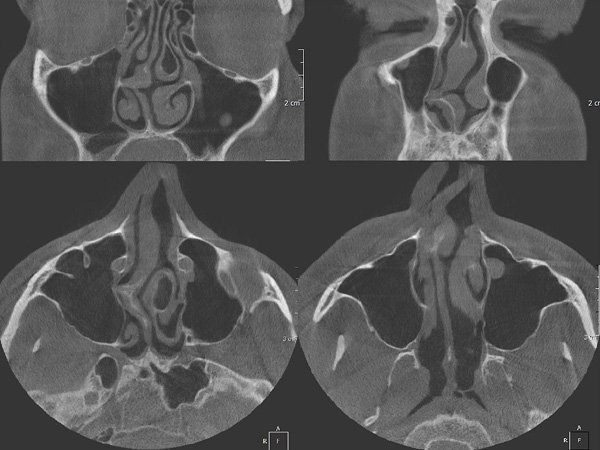

Burun bo'shlig'ining burun septumining rentgenogrammasi Ko'p hollarda burunning nafas olishiga, horg'inlikka, qon ketishiga va tez-tez takrorlangan burun tiqilishi yoki quruqligiga egri burun septumining natijasidir.

Burun burun septum Va hozirgi paytda, ko'plab tekshiruvlar va o'tmishda o'tkazilgan operatsiya vaqtida, septoplastikadan keyin bemor qayta tiklanish davri boshlanadi va yana ikki qismga bo'linadi: